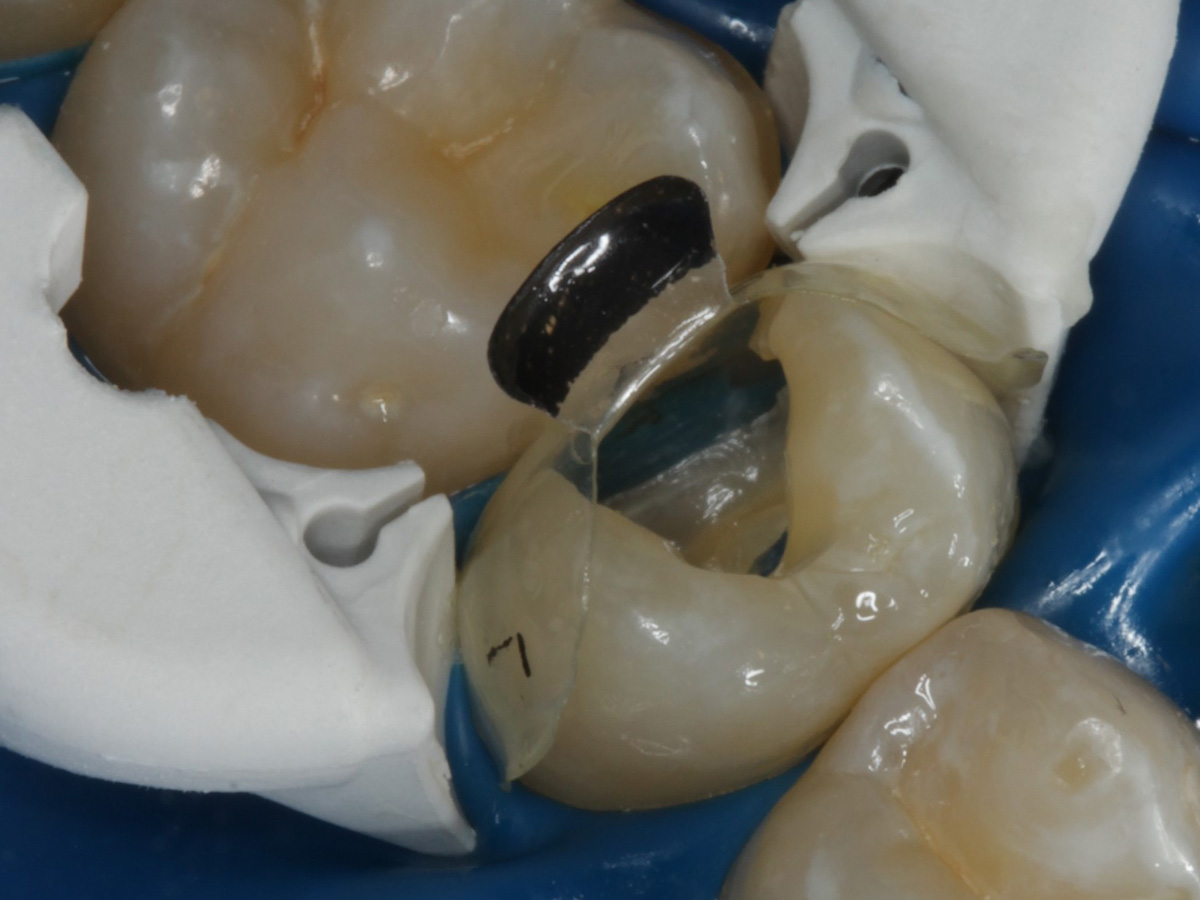

Abbildung 9

Nach Applikation der Matrize: Evolve Schwarz Prämolar- 7 mm; Schmelzätzung